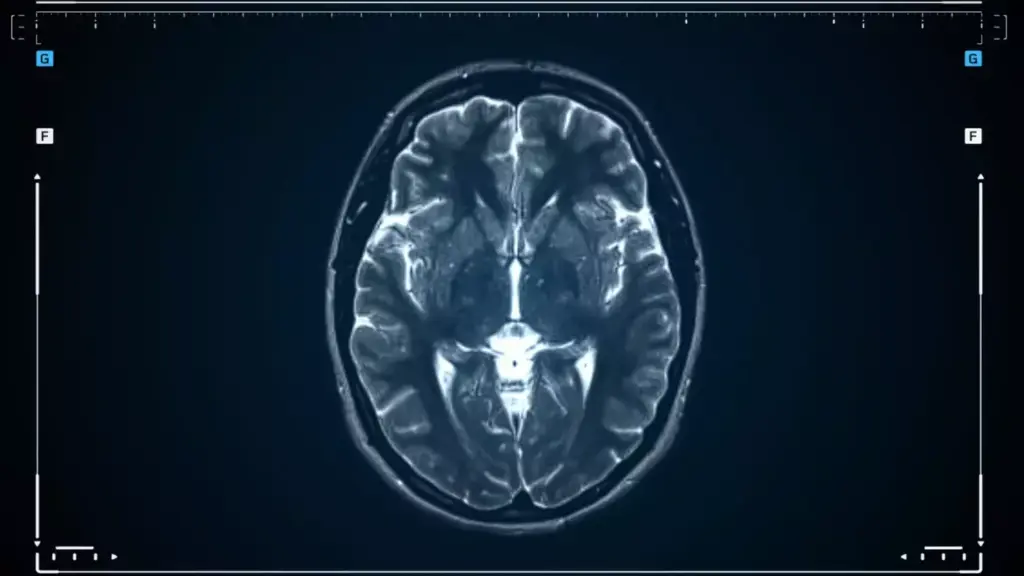

Diagnostic Procedures and Tests

Diagnosing brain cancer requires several tests and procedures. Advanced imaging techniques are key in this process.

- MRI (Magnetic Resonance Imaging): Gives detailed brain images, helping spot tumors.

- CT Scan (Computed Tomography): Uses X-rays to create brain images, useful for finding tumors and bleeding.

- Biopsy: Involves removing tissue for examination to identify the tumor type.